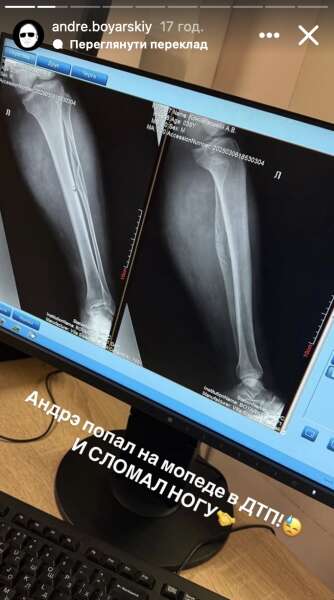

Після інциденту Боярський стояв на обох ногах, але скаржився на біль у нозі, хоча показував, як може рухати нібито постраждалою ногою. Пізніше його доставили в лікарню, де лікарі зробили рентген.

Виявилося, що блогер зламав ногу. Постраждалу кінцівку зафіксували гіпсовою пов’язкою, з якою Боярському доведеться ходити протягом півтора місяця.